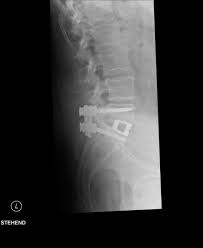

Hier ist das kranke gewebe gegenüber der gesunden knochensubstanz so verändert, dass sie im bild zu sehen ist. Beginnende degeneration des facettengelenkes l5/s1 rechts. Mrt bilder kniegelenk sind musik in den ohren. Mrt der lws t2 (linkes bild) weiß kann man die entzündung der lendenwirbelsäule erkennen, da die bandscheibe durch die fehlstellung aufgebraucht wurde und nun knochen auf knochen reibt und eine entzündung des knochens entsteht. Hier finden sich in der regel typische zeichen. Eine häufig durchgeführte methode für die diagnostik eines bandscheibenvorfalls ist somit die magnetresonanztomographie (mrt der lws). Mrt der lws t2 (linkes bild) weiß kann man die entzündung der lendenwirbelsäule erkennen, da die bandscheibe durch die fehlstellung aufgebraucht wurde und nun knochen auf knochen reibt und eine entzündung des knochens entsteht. Ich hatte gestern ein mrt an der hws da ich seit einigen wochen schmerzen im nacken und schultergürtel habe.

Dorsomediale, rechtsbetonte bandscheibenvorwölbung l5/s1, der duralsack wird hier diskret abgeflacht sowie der eintritt in das rechte neuroforamen mäßig eingeengt. Beginnende degeneration des facettengelenkes l5/s1 rechts. Verdacht auf bursitis hat sich nicht bestätigt, das mrt hüften waren o.b. Mrt der lws t2 (linkes bild) weiß kann man die entzündung der lendenwirbelsäule erkennen, da die bandscheibe durch die fehlstellung aufgebraucht wurde und nun knochen auf knochen reibt und eine entzündung des knochens entsteht. Mrt der halswirbelsäule in sagitaler projektion. Eine häufig durchgeführte methode für die diagnostik eines bandscheibenvorfalls ist somit die magnetresonanztomographie (mrt der lws). Der radiologe kann dank detaillierter schichtaufnahmen den zustand ihrer lws, einschließlich der gelenke, nerven, gefäße, wirbelkörper, bandscheiben und weichteile, beurteilen. Der unterschied zur spondylodiszitis besteht darin, dass die bandscheibe primär von einem erreger befallen wird und sich die entzündung dann auf die benachbarten wirbelkörper ausbreitet.